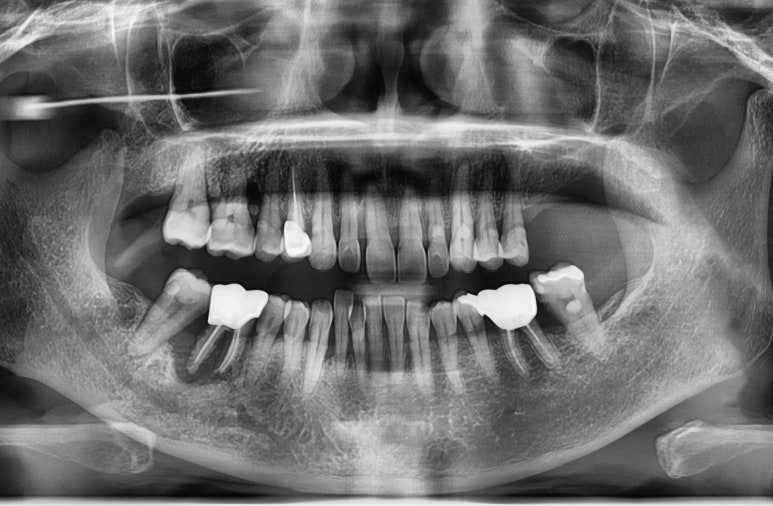

더 정확하고 안전한 임플란트식립을 위한

네비게이션임플란트

오른쪽:시술오차 가능성이 적은 내비게이션임플란트

시청역 연세예감치과에서 실제 시행한 내비게이션임플란트에 대한 모의시술사진